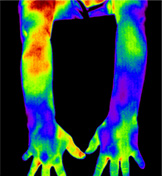

적외선 체열검사 DITI (Digital Infrared Thermal Imaging)

- X-ray, MRI 등으로 확인할 수 없는 신경통, 근육통 등을 확인하기 위하여 적외선을 이용하여 체열 분포의 변화를 확인하는 검사

- 통증이 있는 부위에서는 교감, 부교감 신경의 작용으로 체열이 높거나 낮게 측정되므로 이러한 변화를 측정하여 정확한 통증 부위를 확인 가능

질병에 따른 DITI 분석

테니스 엘보우